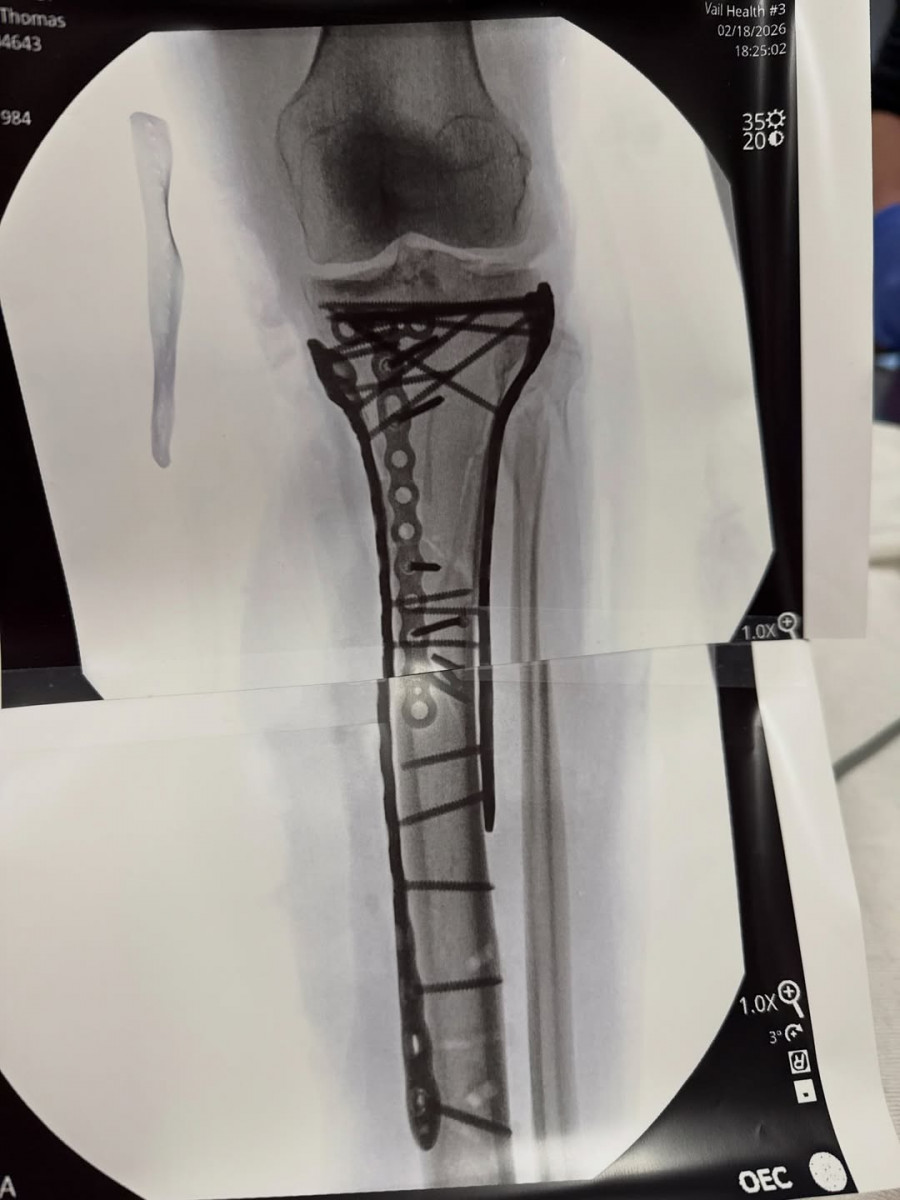

Η 41χρονη Ολυμπιονίκης ενημέρωσε τους διαδικτυακούς της φίλους μέσα από το νοσοκομείο, λίγες ημέρες μετά την επιστροφή της στις Ηνωμένες Πολιτείες. «Τα κατάφερα στο χειρουργείο… κράτησε λίγο περισσότερο από 6 ώρες. Όπως μπορείτε να δείτε, χρειάστηκαν πολλές λάμες και βίδες για να αποκατασταθεί η ζημιά, αλλά ο Δρ. Hackett έκανε εξαιρετική δουλειά», έγραψε σε ανάρτησή της στο Instagram, δημοσιεύοντας βίντεο από τη μεταφορά της με φορείο, φωτογραφία με τα υλικά οστεοσύνθεσης και ακτινογραφίες της κνήμης της γεμάτης μεταλλικά στηρίγματα.

Η ακτινογραφία της κνήμης της Βον μετά την πολύωρη επέμβαση, με λάμες και δεκάδες βίδες που τοποθετήθηκαν για την αποκατάσταση του σύνθετου κατάγματος